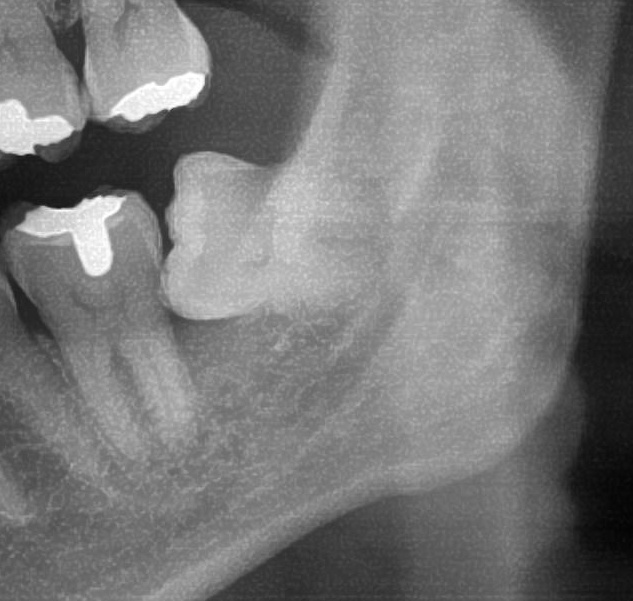

次にパノラマ写真を撮影してみると、左下の親知らずは手前の歯を押すように斜めに生えているのが確認できました。

さらに、下顎の親知らずは下歯槽神経に非常に近いところに生えている場合もあるため、CTも撮影し詳しい解析を行います。

親知らずが生えている位置が、神経に近い、あるいは神経に当たっている場合は、大きな病院に紹介する場合もあります。

親知らずの根っこは下歯槽神経から近い距離にありますが、抜歯は可能との診断でした。